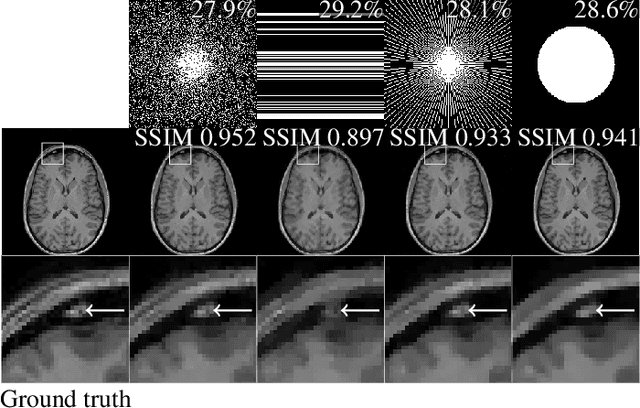

Abstract:The discovery of the theory of compressed sensing brought the realisation that many inverse problems can be solved even when measurements are "incomplete". This is particularly interesting in magnetic resonance imaging (MRI), where long acquisition times can limit its use. In this work, we consider the problem of learning a sparse sampling pattern that can be used to optimally balance acquisition time versus quality of the reconstructed image. We use a supervised learning approach, making the assumption that our training data is representative enough of new data acquisitions. We demonstrate that this is indeed the case, even if the training data consists of just 5 training pairs of measurements and ground-truth images; with a training set of brain images of size 192 by 192, for instance, one of the learned patterns samples only 32% of k-space, however results in reconstructions with mean SSIM 0.956 on a test set of similar images. The proposed framework is general enough to learn arbitrary sampling patterns, including common patterns such as Cartesian, spiral and radial sampling.